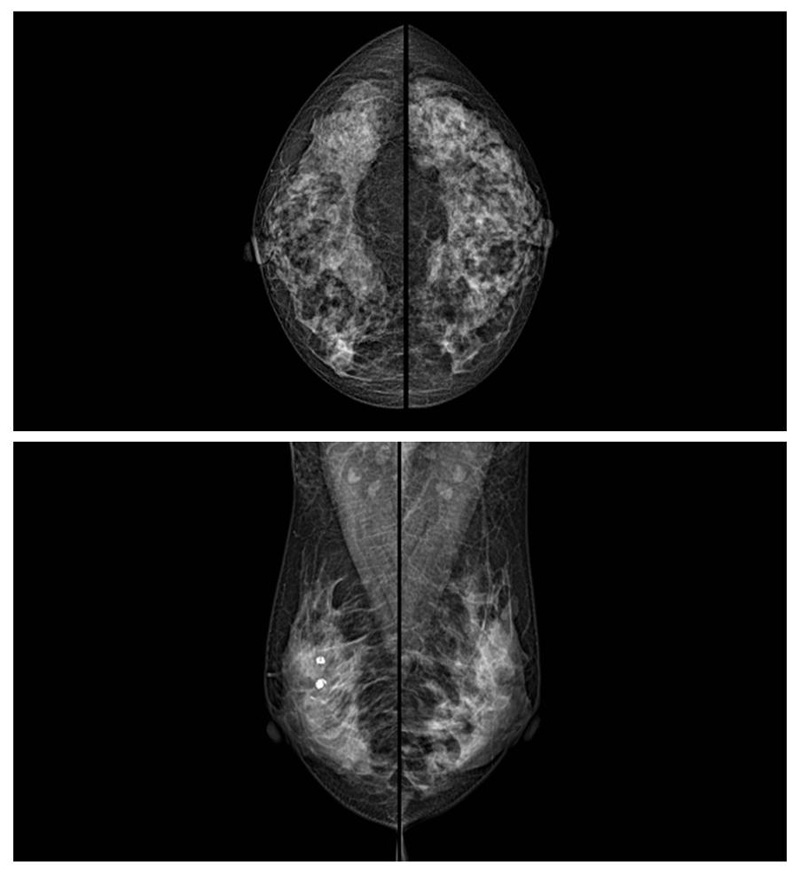

乳腺癌的發(fā)生率越來越高,已經(jīng)是我們國(guó)家的癌癥之一已成為女性健康“頭號(hào)殺手”。乳腺DR可提高乳腺癌早期檢出率并精準(zhǔn)定位。發(fā)現(xiàn)和診斷早期乳腺癌最有效的方法之一,明顯利大于弊女性都要重視乳腺的檢查。輻射很小最簡(jiǎn)便、最可靠、無創(chuàng)性檢查手段,做一次乳腺DR的劑量相當(dāng)于7周的正常生活。尤其是對(duì)于40歲以上的女性尤為重要,那么乳腺DR是怎么進(jìn)行檢查的呢?我們來了解一下,為廣大朋友在檢查前有點(diǎn)心理準(zhǔn)備。檢查時(shí)候是避開經(jīng)期的前后,月經(jīng)來后的7天左右比較合適。需要脫衣服檢查,根據(jù)拍片的擺位要求,有頭尾位置,內(nèi)外斜位,還有側(cè)位。定點(diǎn)放大壓迫方法可以更細(xì)微清晰的檢查出病灶。